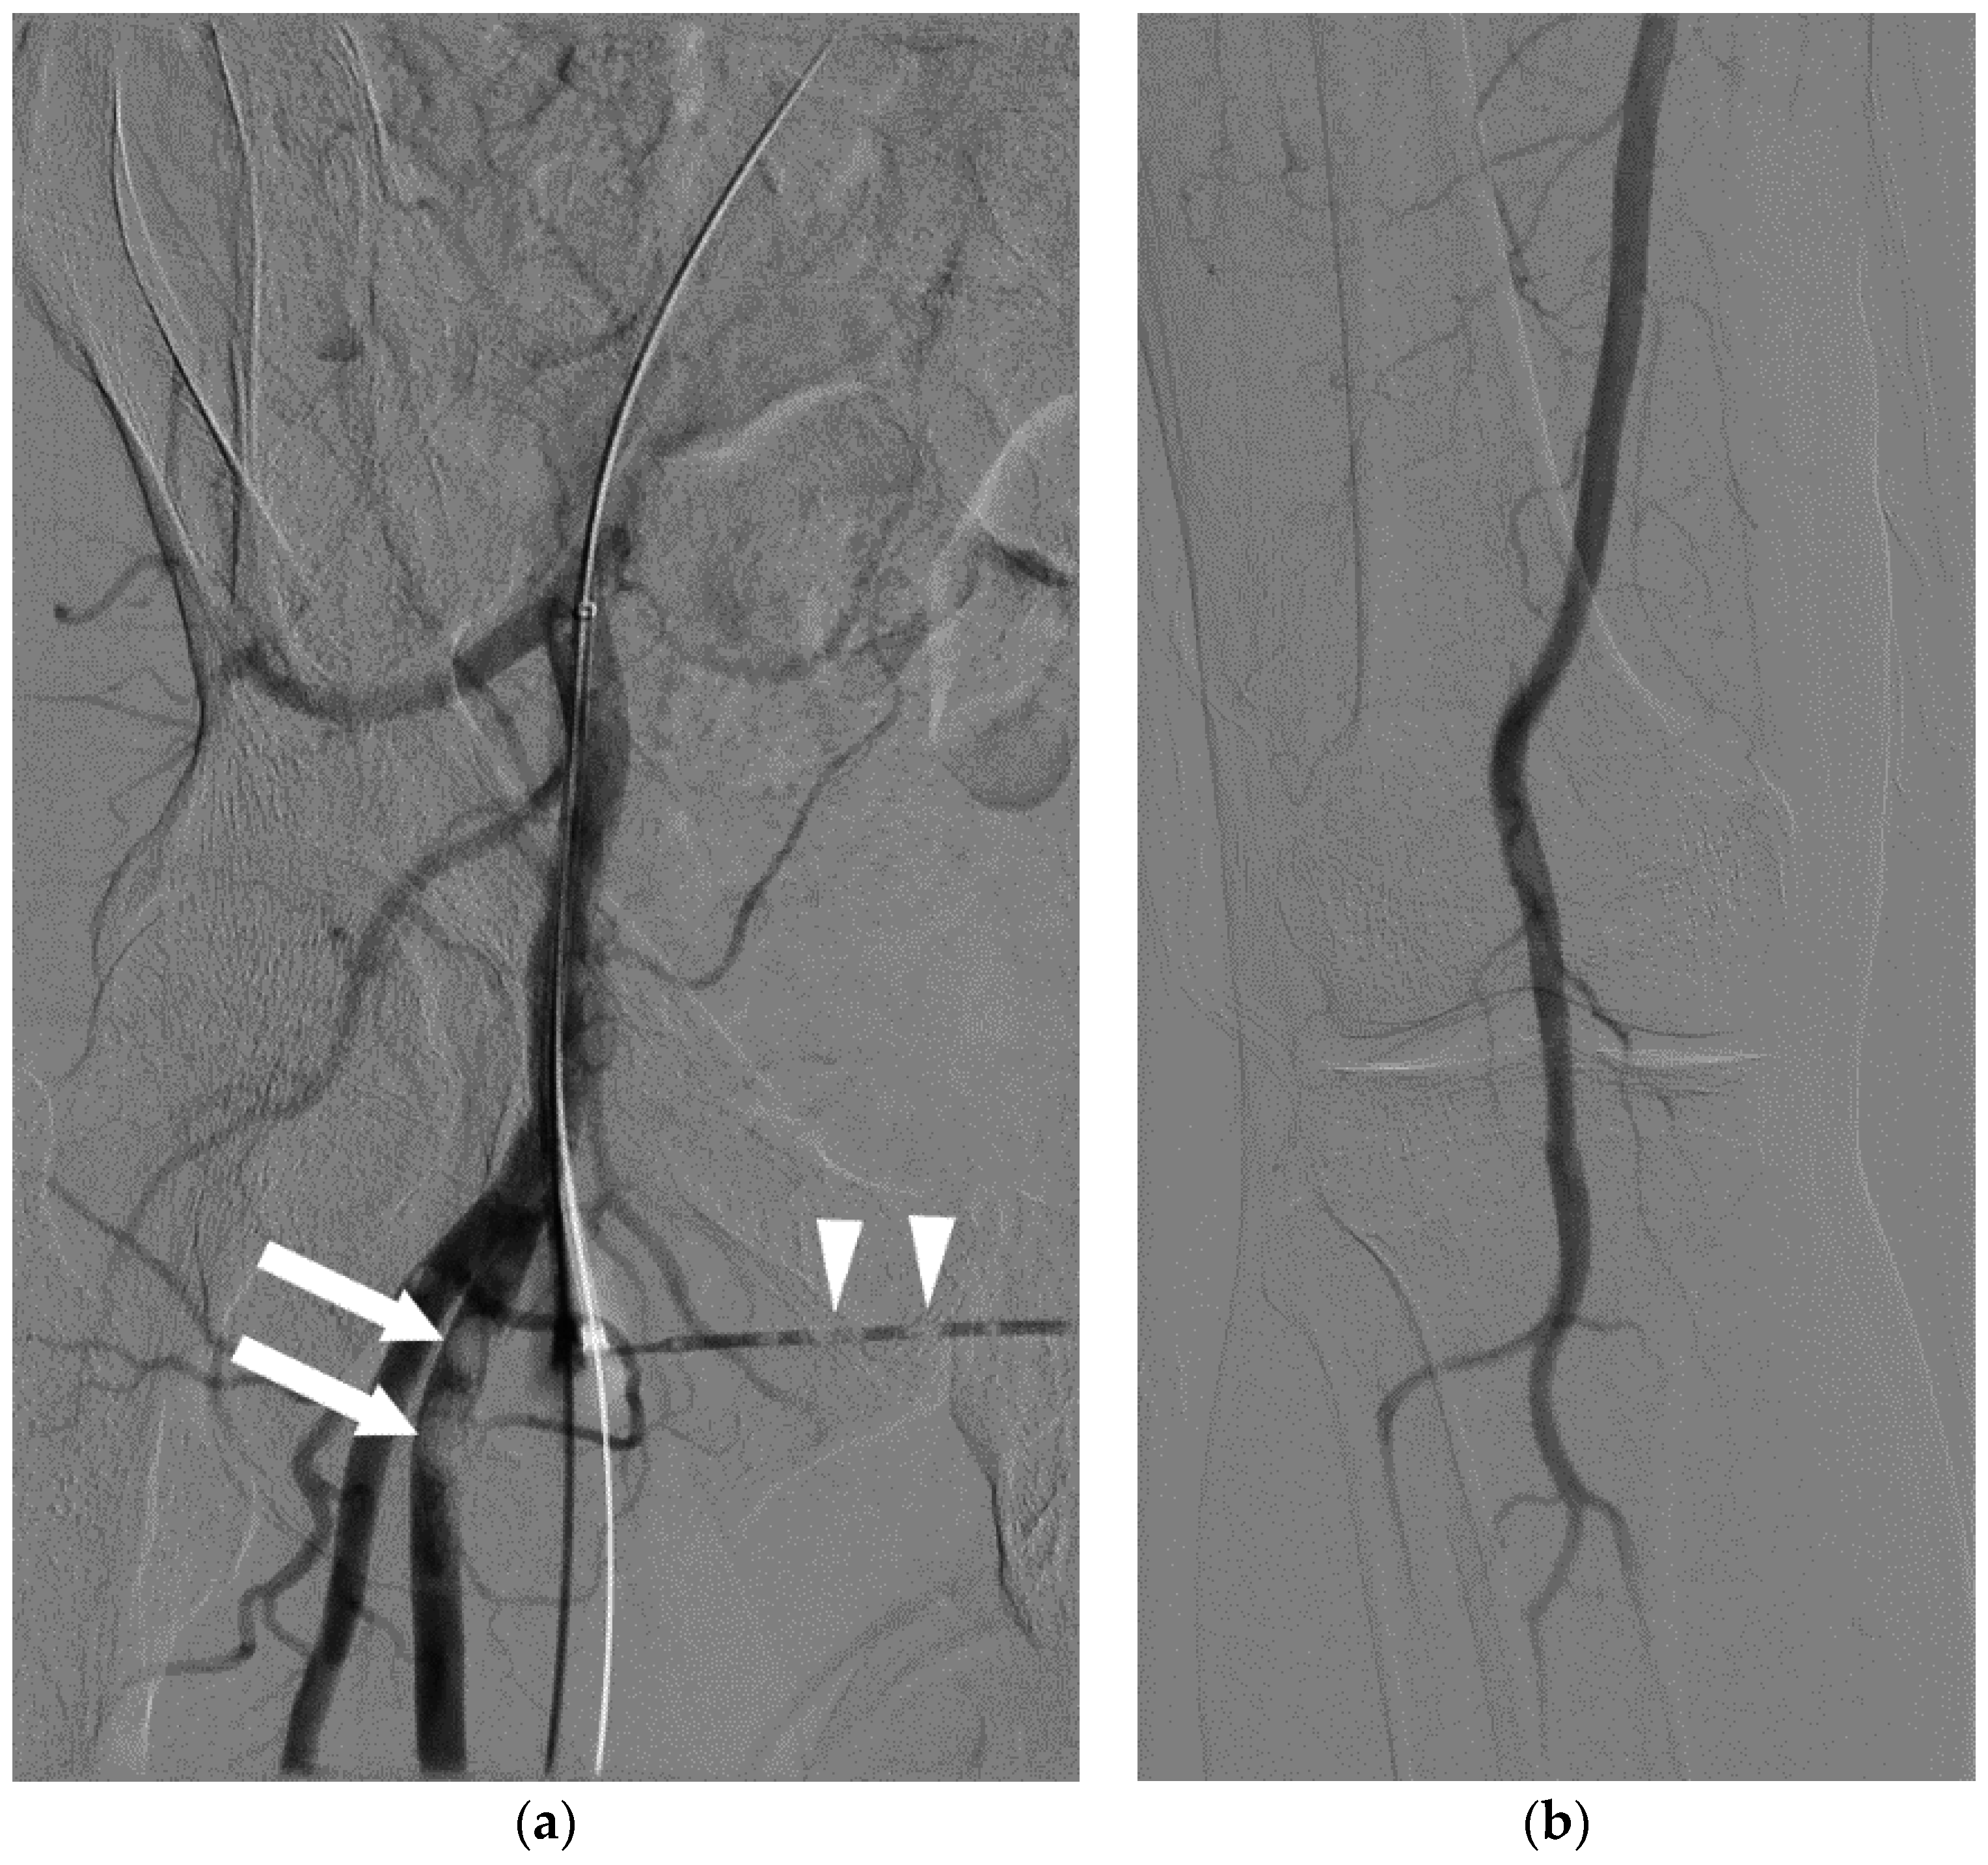

4.2. During an Angiogram or Other Invasive Procedure

5.2. Advanced Management

5.3. Air Aspiration